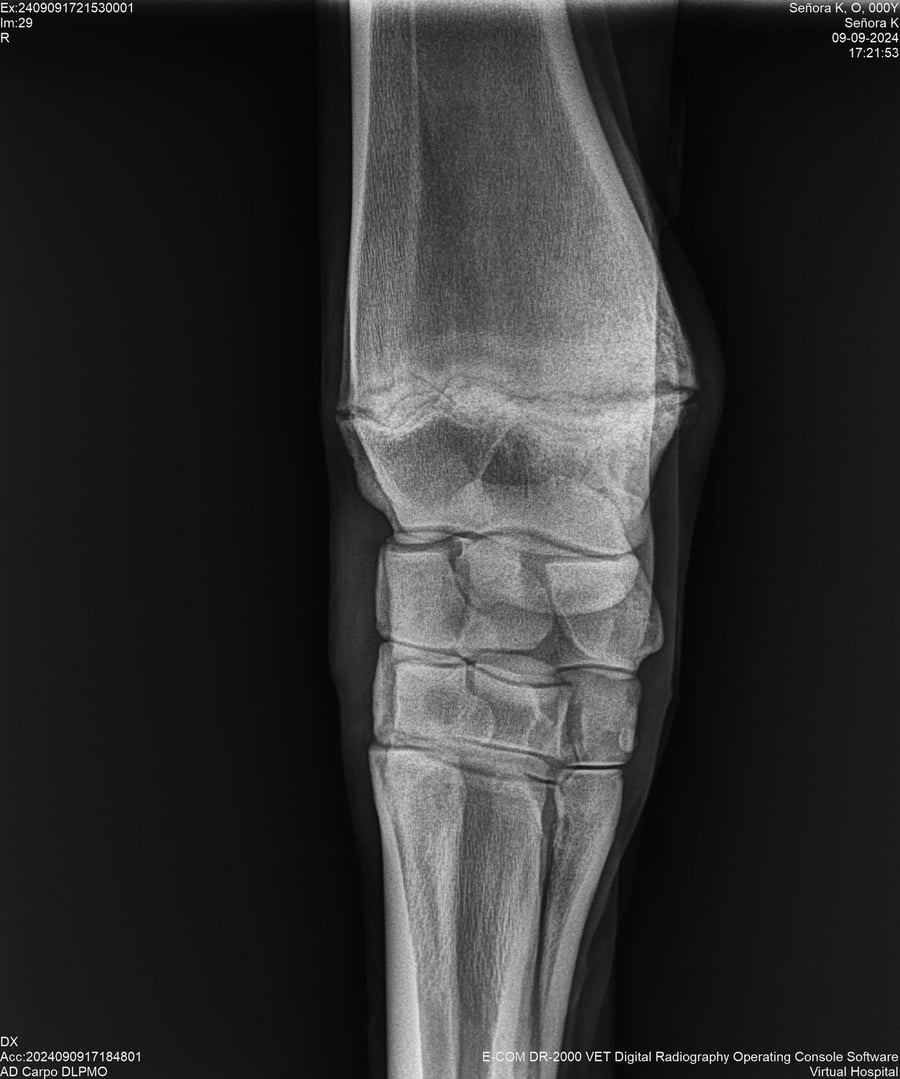

LOTE 44, SEÑORA K

Identificador: #291147-

Generacion 2022